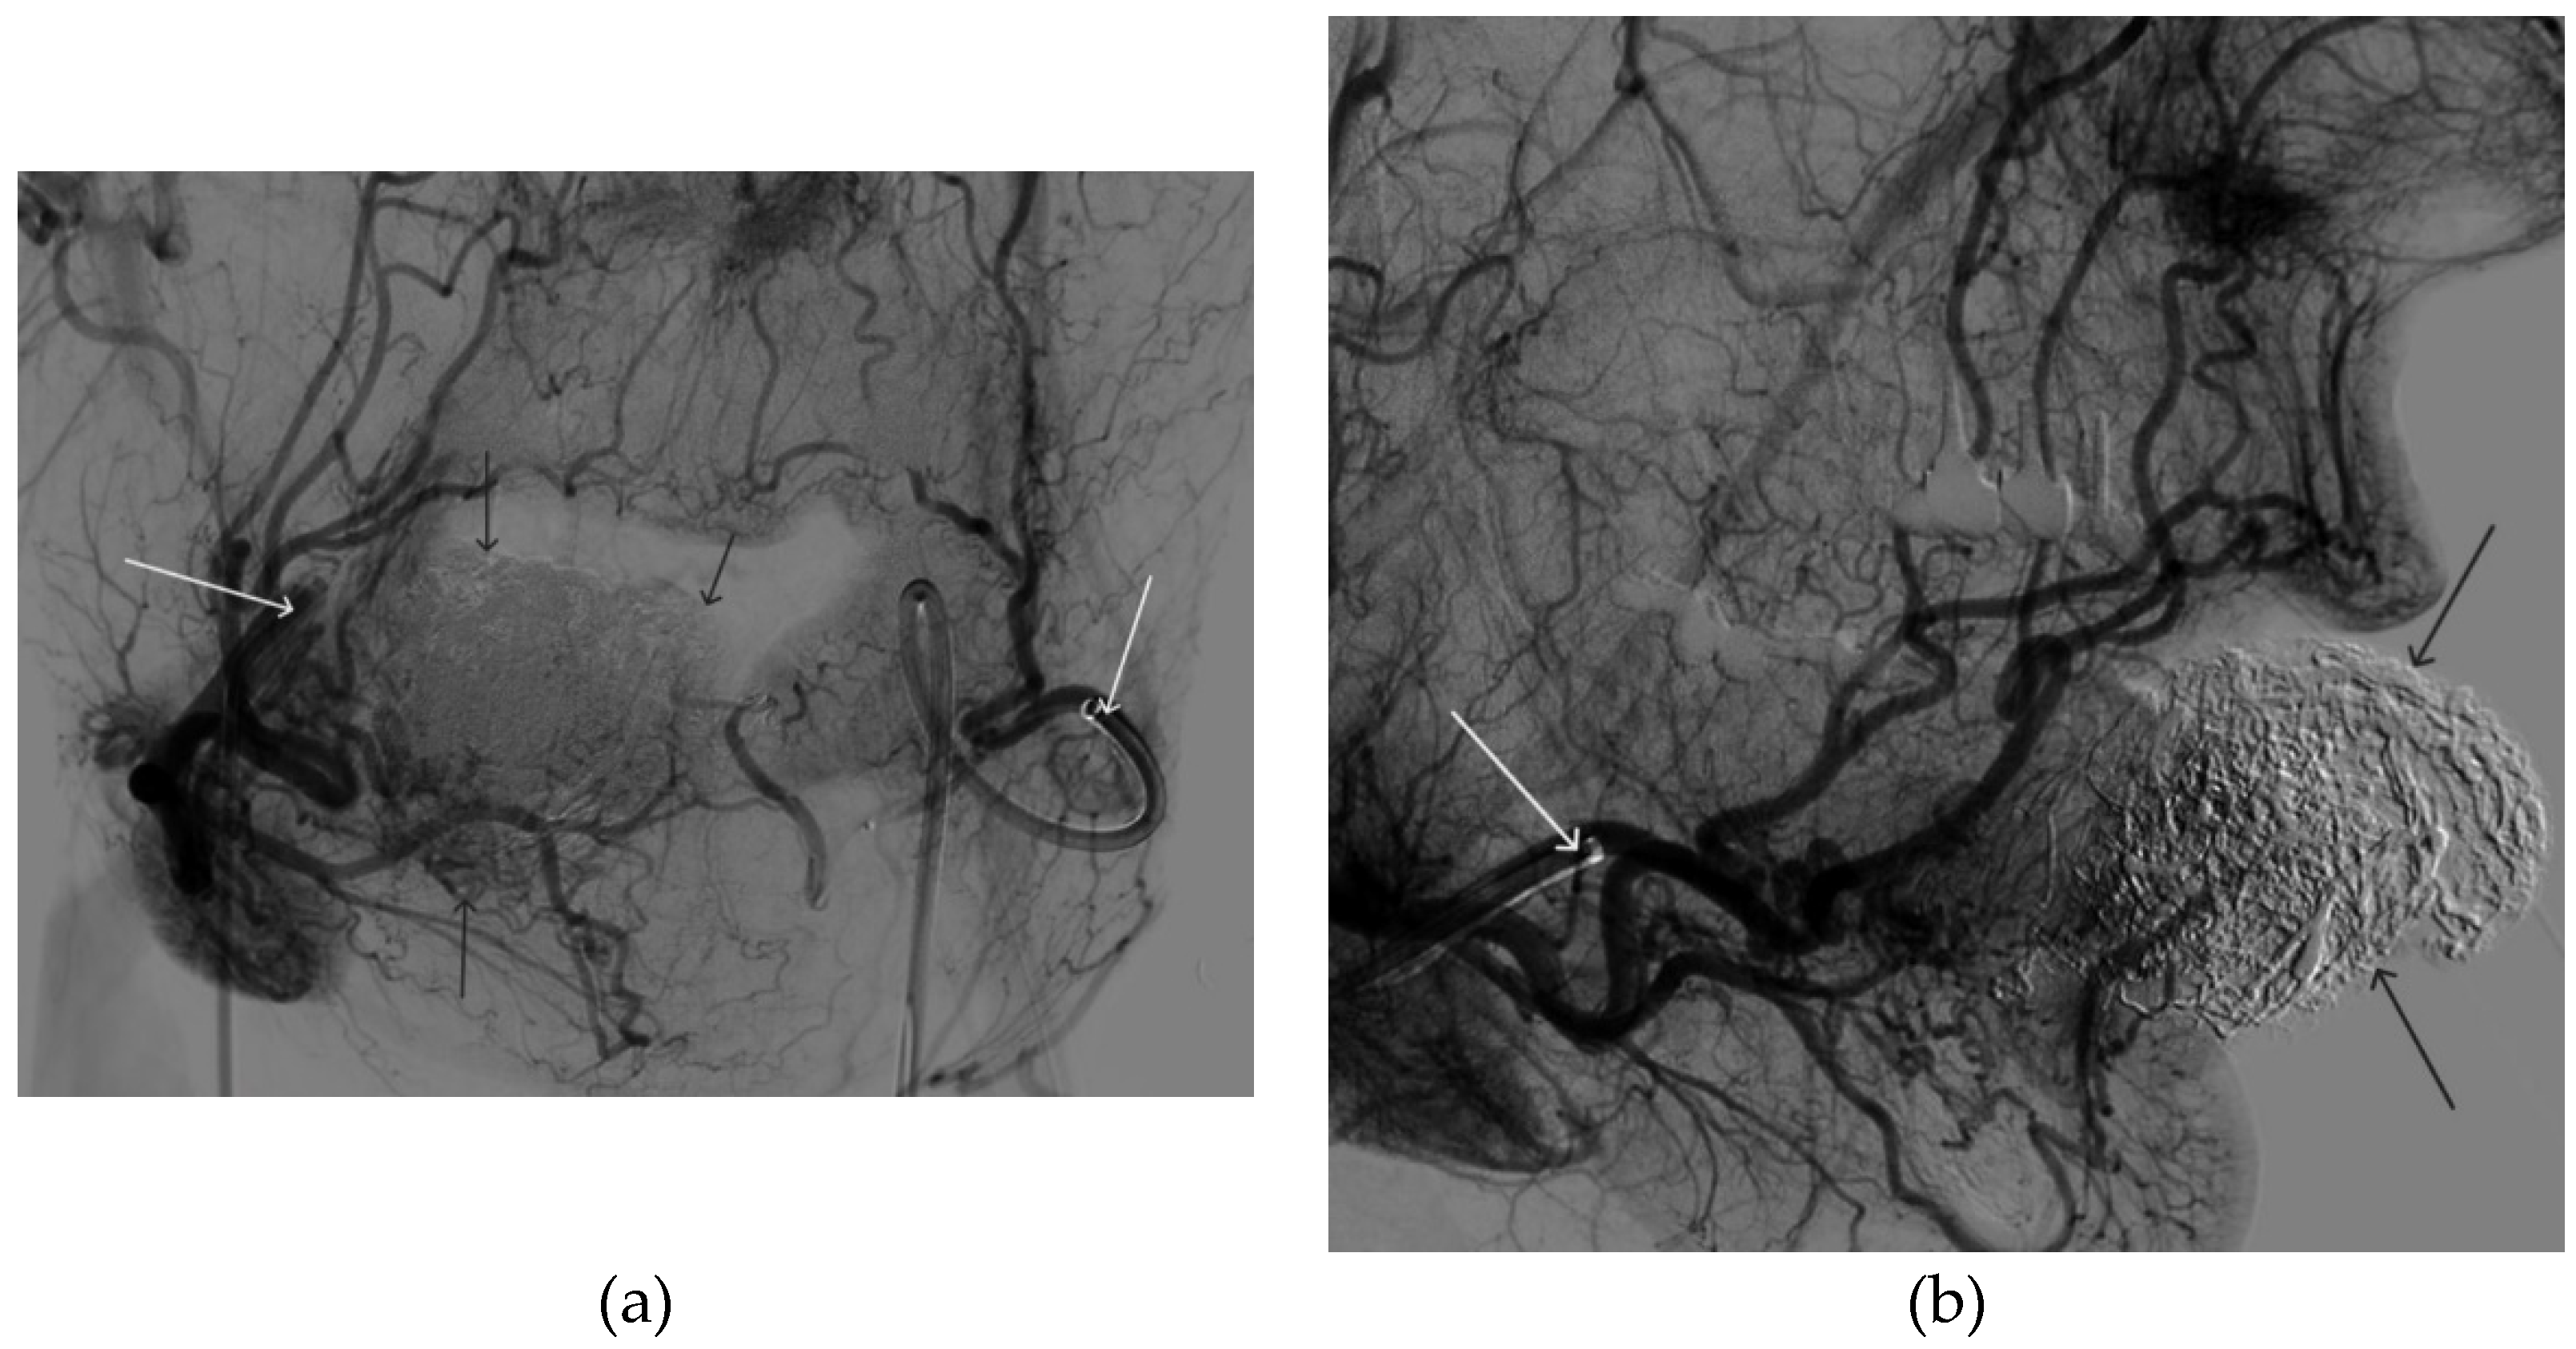

Figure 12. Distribution of Onyx-18 along the vascular network of the paraganglioma: a – direct projection, b - lateral projection (white arrows indicate filling of the vascular network of the paraganglioma, black arrows indicate an inflated balloon in the left internal carotid artery).